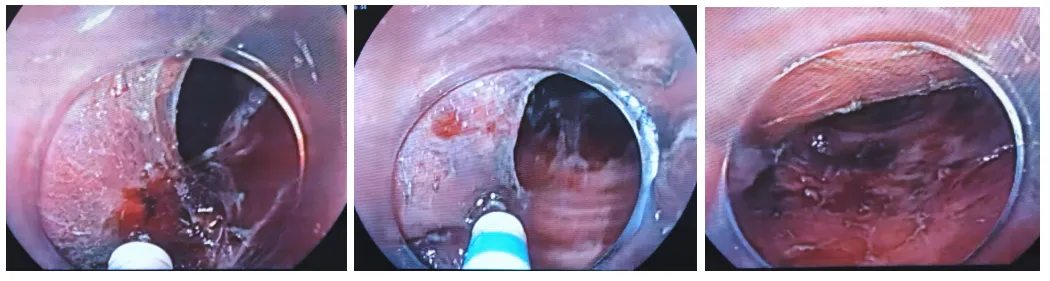

9:58Dual刀粘膜下补水后继续从上往下剥离(有时会换粘膜注射针注射,隆起会比较好一些),粘膜下层非常溥,水垫很快消失。

10:05-14当剥离到困难时,有时也会用牙线或圈套器或“O”型圈内牵引,用“口袋法”自身牵引也可以。有些地方纤维化非常明显,现在是利用重力往下牵引剥离

10:41这个病灶纤维化很明显,粘膜下注射水垫只给我们切一刀,水垫就消失了。10:44遇到血管,先裸化,用热止血钳电凝再切断。

10:53左侧这部分粘连比较严重,这里好几个地方都是偏低位,可能需要改变体位或用到牵引